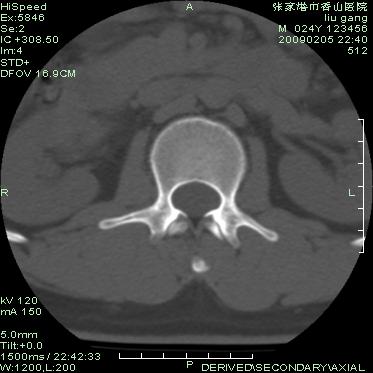

以下是引用随光逐影在2009-3-11 14:43:00的发言:[br]平片:l3、4、5及s1前上缘见类似“切角征”。[br]ct扫描:腰椎多个节段椎间盘向椎体内(椎体前部)突出。